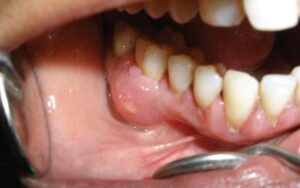

| Áp xe nướu | Khu trú ở mô nướu, thường do dị vật/kẹt thức ăn hoặc chấn thương nướu | Sưng khu trú như một điểm mủ ở nướu; đau tại chỗ, dễ khó chịu khi chạm; vẫn nên khám để loại trừ nguyên nhân sâu bên dưới |

- Nướu sưng, có điểm sưng như “mụn” hoặc chảy mủ.